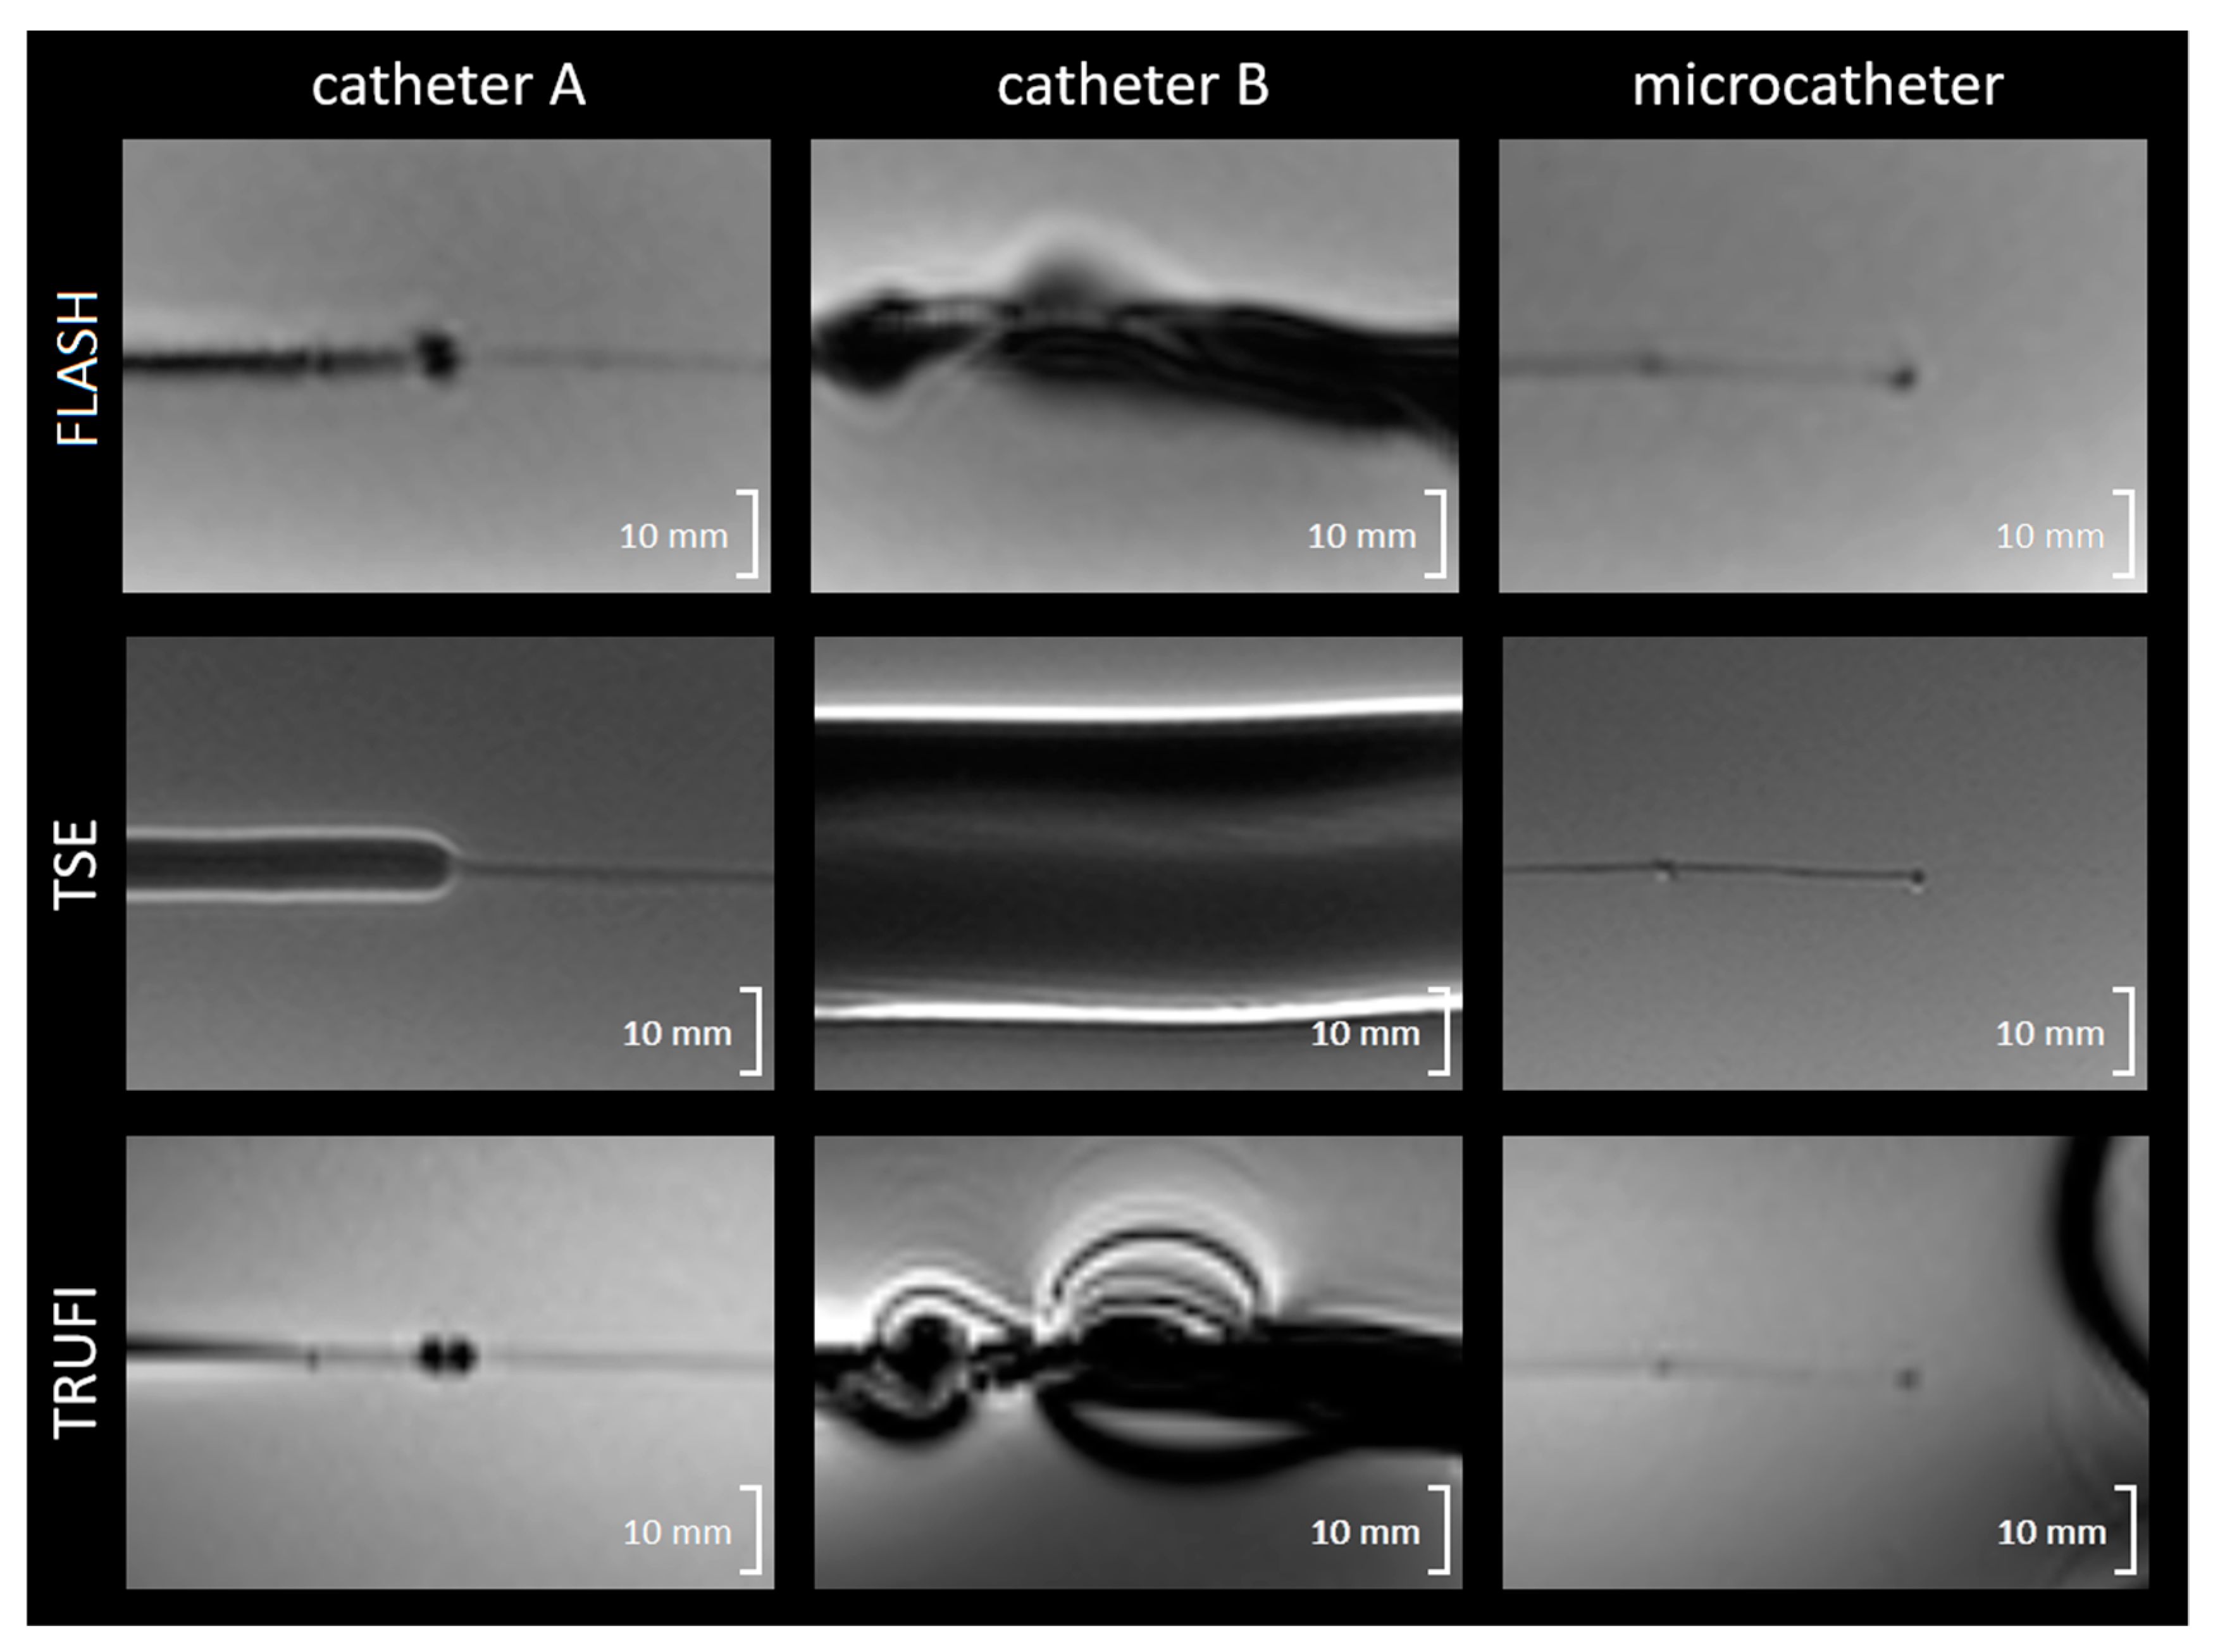

2.1.2. Magnetically Induced Displacement and Artefact Size

3.2. Magnetically Induced Displacement and Artefact Size

3.3. In Vivo Artefact Size